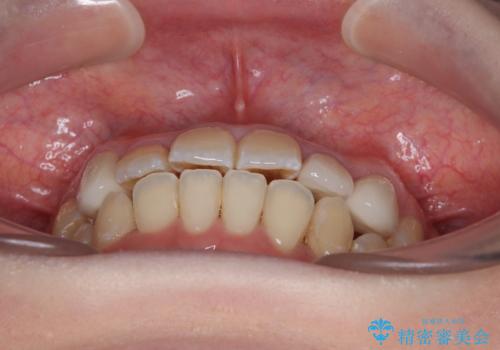

矯正治療後は全顎的にむし歯が多いため、セラミッククラウンやインレーにより補綴治療を行うこととしました。

急速拡大が奏効し、非抜歯矯正にて八重歯を解決することができました。